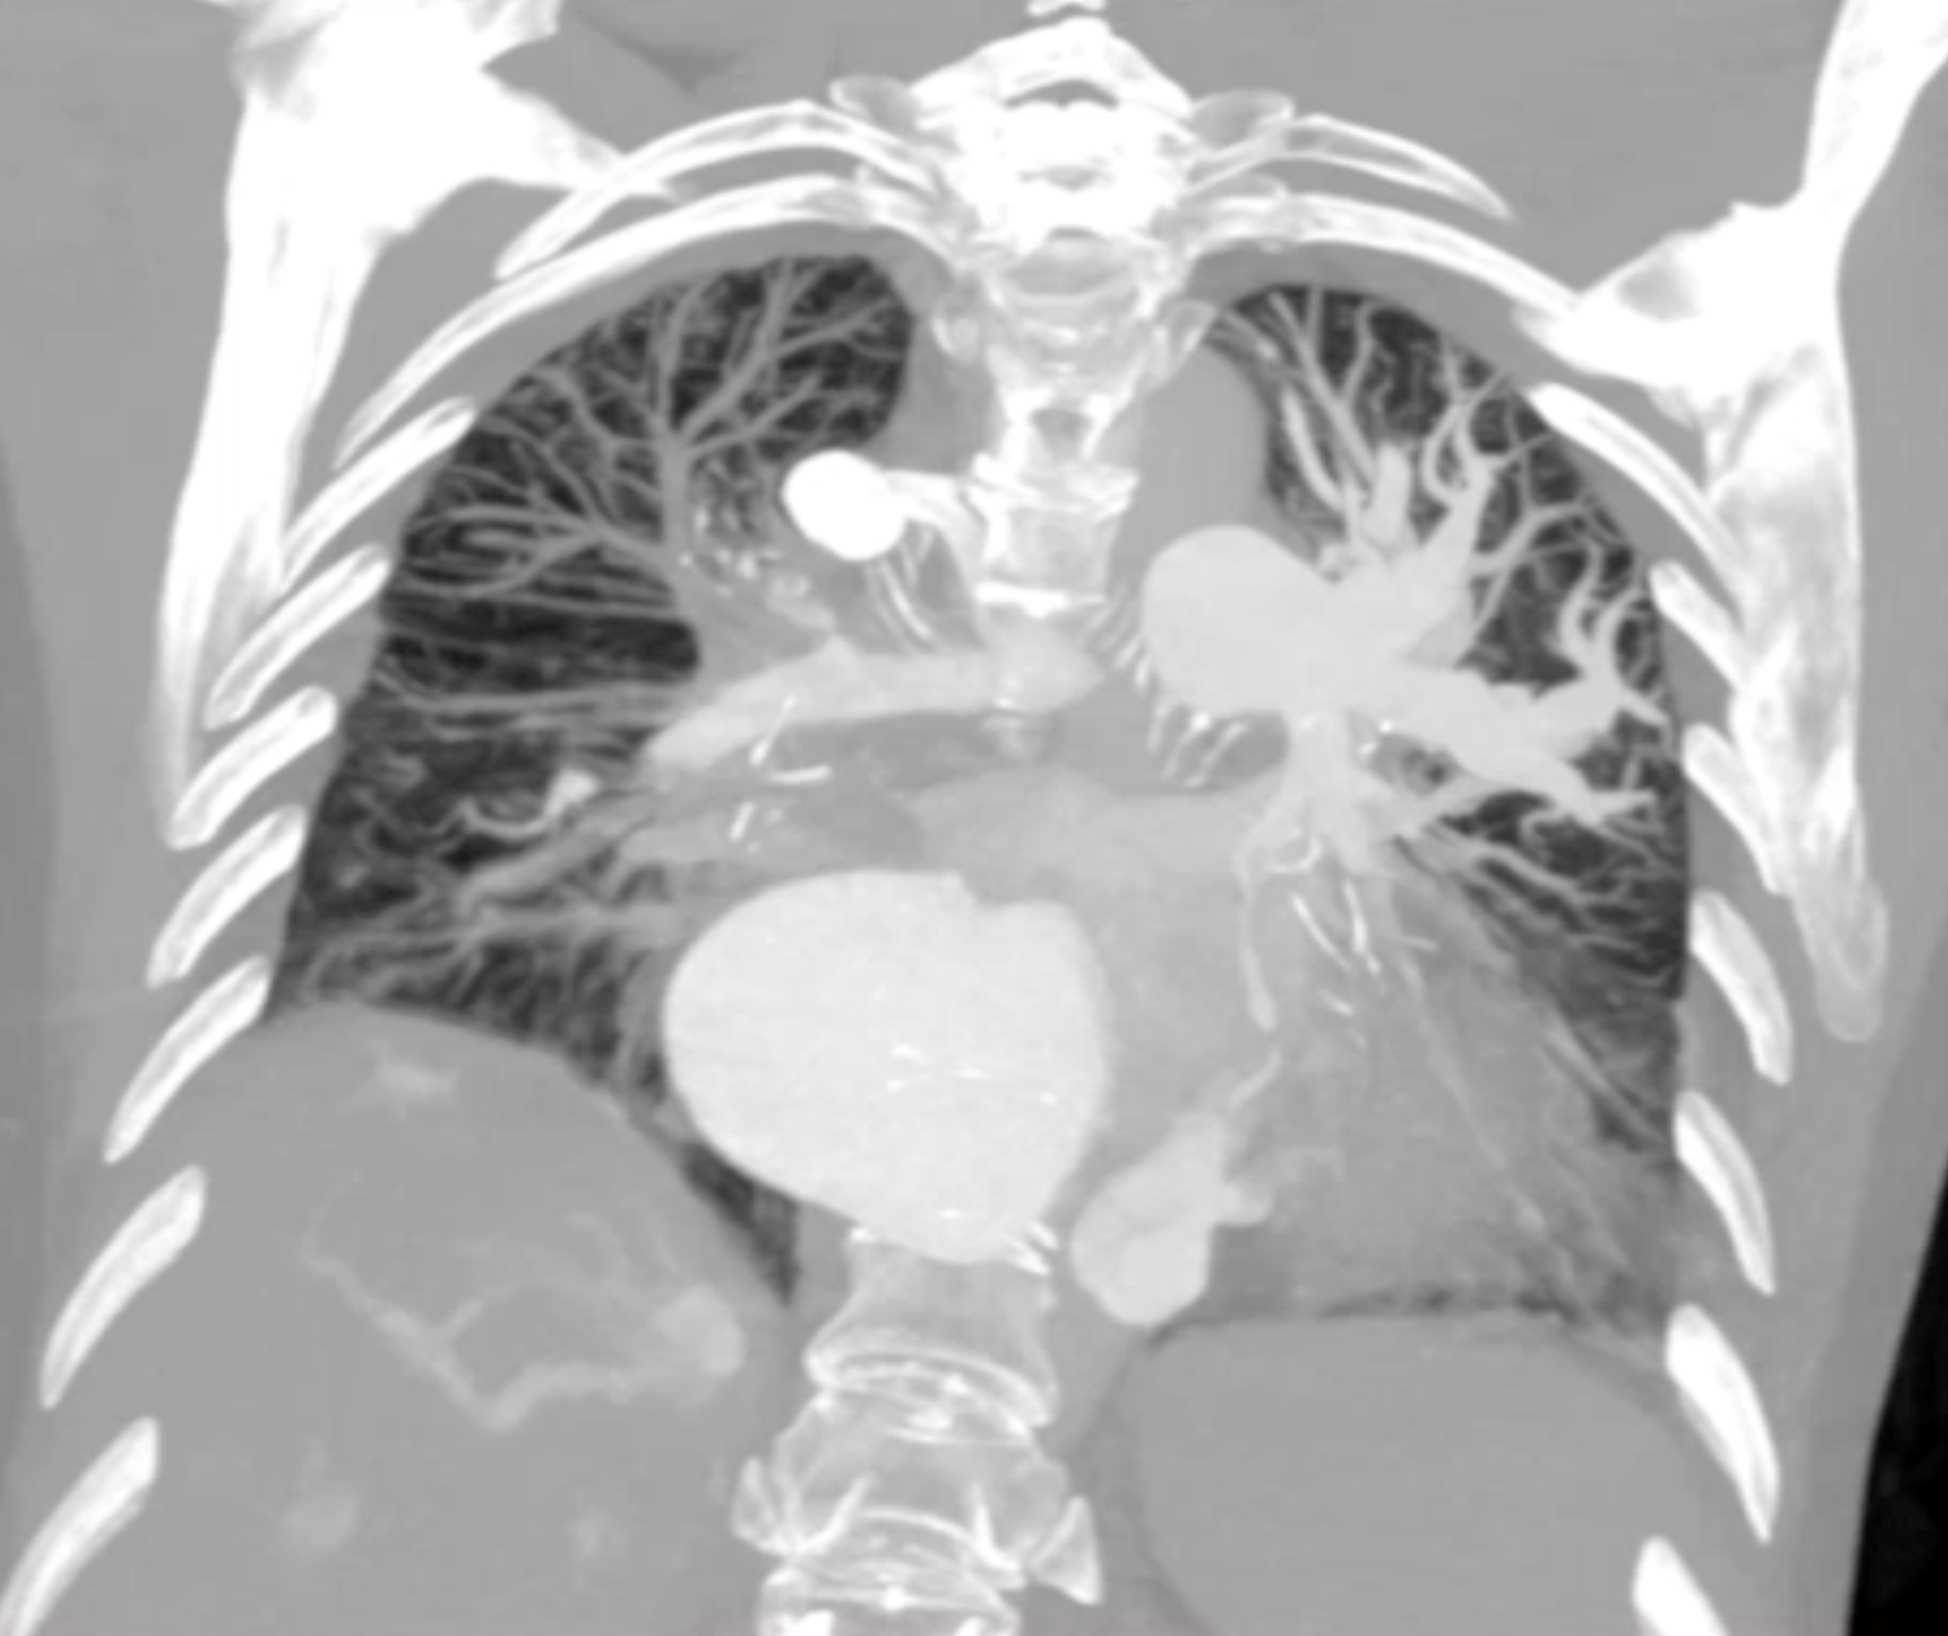

Fibrosing Mediastinitis involves the Pulmonary Artery and Vein